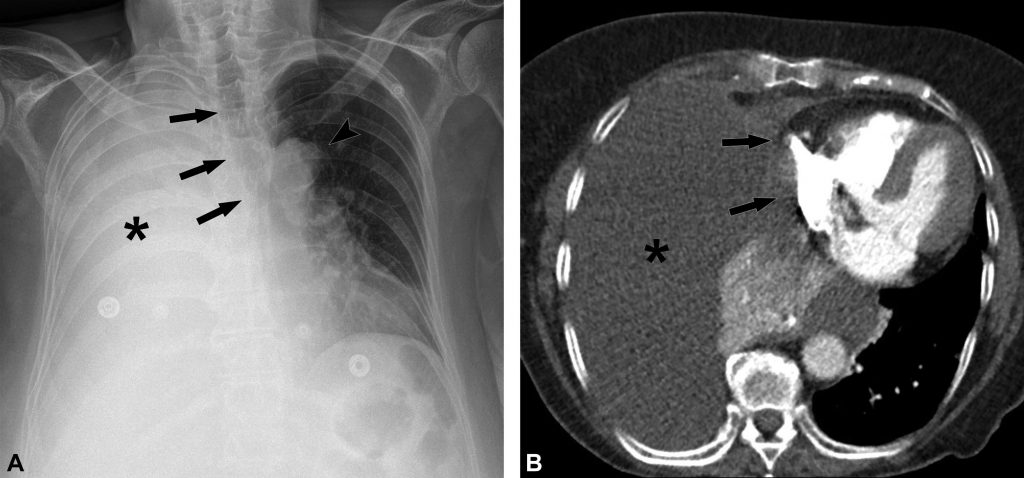

Fig. 91.2. Radiographie de face debout et scanner non injecté d’un épanchement pleural gauche de grande abondance.

L’opacité hydrique déclive de la base de l’hémithorax gauche, efface le diaphragme et le bord gauche du cœur. Elle présente une limite supérieure concave vers le haut et vers l’intérieur, réalisant une ligne de Damoiseau (flèches en A). Le scanner chez le même patient montre l’épanchement de grande abondance (astérisque en B) déclive avec une limite concave vers le haut et vers l’intérieur (flèches).

Source : CERF, CNEBMN, 2022.